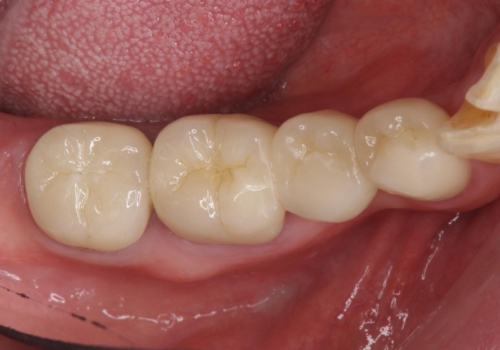

70代女性 状態の悪い歯を抜歯して、奥歯をブリッジに

- 他院で右下小臼歯が保存不可能と言われ来院。当院の判断でも残念ながら抜歯となり、欠損部は抜歯後ブリッジにしました。右下奥2本が連結されていたため、そこは各々切り離した形で被せ物のやり替えも行っています。

抜歯後3か月ほど仮歯で生活していただき、欠損部の歯肉の状態が安定してからブリッジを入れています。